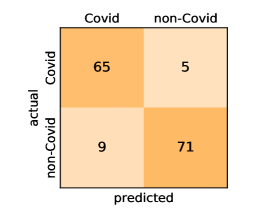

Here, we present and discuss the obtained results for detecting COVID-19 on the considered CT image datasets with different deep networks. We report the quantitative results along with the confusion matrices for every single architecture of the adopted networks.

On the SARS-CoV-2 CT dataset, ResNet101 achieves the best overall performance with respect to almost all evaluation metrics, with an average accuracy and F1-score of and , respectively. The model also achieves an average sensitivity rate of indicating that, on average, only two COVID-19 images are falsely predicted as negatives. It is also powerful enough to correctly identify all Non-COVID-19 cases with only one false positive resulting a specificity rate of . The highest sensitivity score of is achieved by the InceptionV3 model, where only one COVID-19 image is falsely predicted as negative on average. The SqueezeNet model obtains the lowest performance with respect to all evaluation metrics with a fairly acceptable average accuracy and sensitivity scores of and , respectively. Also the ShuffleNet architecture obtains satisfactory performance with approximately improvements on average for all metrics compared with SqueezeNet. Although the results obtained by these models are inferior compared with the rest of models, but they are more efficient. This matches their main objective of reducing the computational costs rather than improving their visual recognition abilities. The rest of models achieve competitive performance and very promising results with slight performance differences. Comparing the different variants of ResNet and DenseNet, we can see that the deeper variants from each architecture yield a slightly better performance. The deeper ResNet101 and ResNeXt101 show a marginal gain in performance compared with their shallower counterparts. The details about class-wise results for each model are summarized in the confusion matrices in Figure 9.

Our models achieve fairly good performance compared with the recently published work using the exact network architectures. This can bet attributed to a better optimization of our models and the effectiveness of our fine-tuning strategy using custom-sized inputs determined specifically for each architecture. Here, we see that DenseNet201 outperforms all other architectures. The model achieves average accuracy and sensitivity scores of and , respectively. It also identifies all COVID-19 images with only four images, on the average, are falsely predicted as Non-COVID-19. DenseNet169 achieves the second best average accuracy of and a very high sensitivity identical to the best model. The DenseNet121 and Xception models have nearly identical results for all evaluation metrics. We observe that small-sized networks such as ResNet18 achieves comparable results with other deeper models. The SqueezeNet and ShuffleNet models perform at a similar level of accuracy. The variants of the ResNeXt models have comparable results and perform as good as the different ResNet variants. A detailed analysis on the class-wise results for individual models is presented in the confusion matrices in Figure 10.